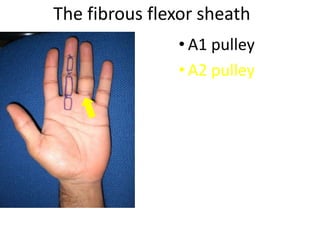

- It describes flexor tendon zones, extensor compartments, and pulley system anatomy.